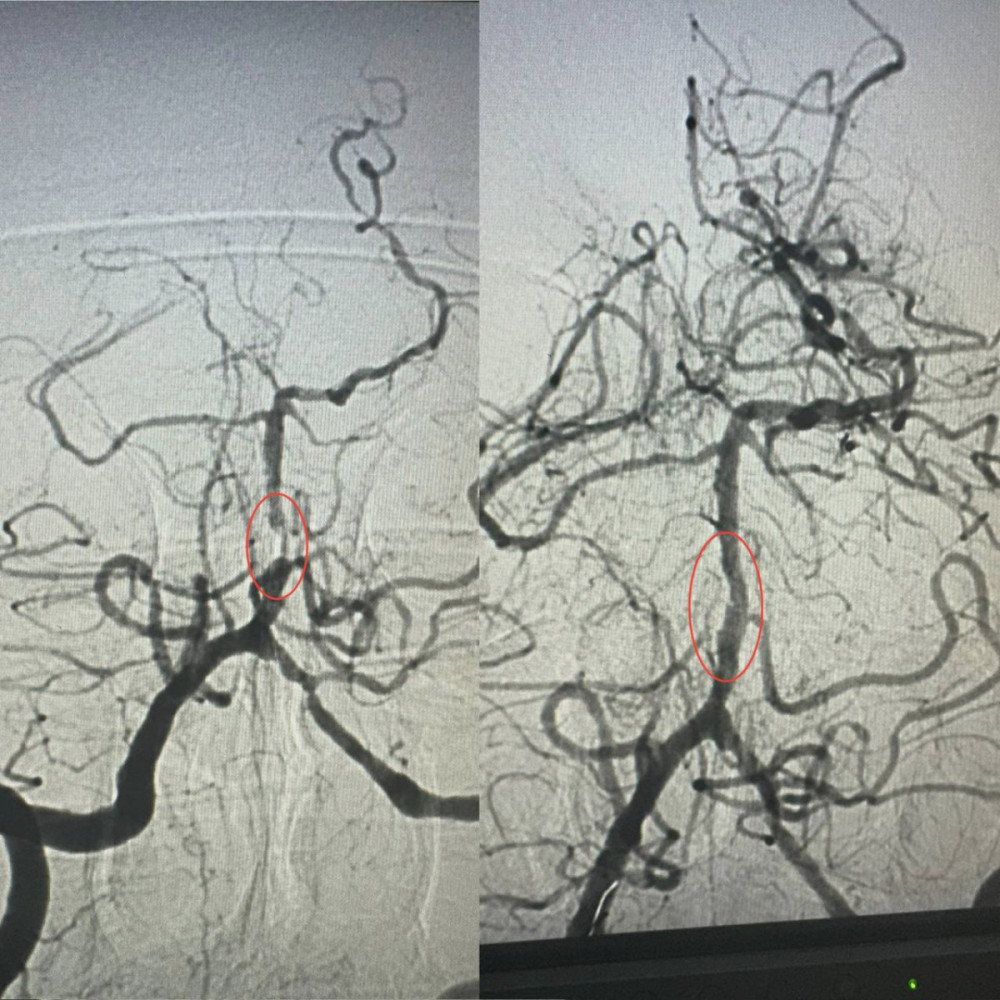

Как рассказал заведующий рентгенэндоваскулярным отделением Александр Скрипка, это был один из самых сложных случаев - поражение ствола головного мозга. Базилярная артерия была почти полностью заблокирована атеросклеротической бляшкой. Такие инсульты относятся к наиболее опасным, а при отсутствии срочной помощи шансы на выживание минимальны.

Специалисты приняли решение провести операцию и выполнить ангиопластику артерии. Больница №10 имеет опыт применения этой методики в кардиологии при атеросклерозе коронарных сосудов, но использование ее для мозговых сосудов является инновационной технологией в Украине.

Операция длилась около часа. Узкая артерия была расширена при помощи специального баллона, а затем использован баллон с лекарственным покрытием.